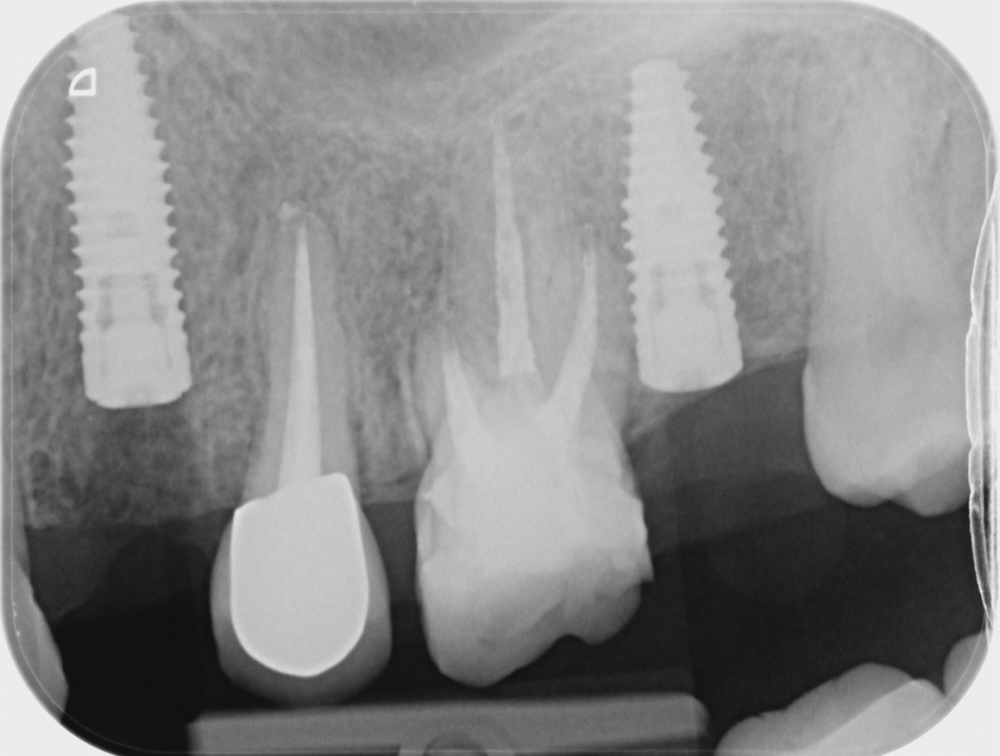

lola-1234 Опубликовано 22 июля, 2021 Поделиться Опубликовано 22 июля, 2021 Здравствуйте, дорогие доктора! Очень нуждаюсь в вашем мнении. Поставили мне сегодня два импланта. Когда увидела снимок установленных имплантов, засомневалась правильно ли врач их установил. Четверка была удалена 2 месяца назад, корни зуба были такой же длинны, что и у пятерки. 1. Как мне кажется, врач установил имплат очень глубоко,под самую гайморовую пазуху. Врач сказал, так как у меня было воспаление после удаление зуба, , поэтому он врутил поглубже, там кость "получше" . Не разумней было бы, просто подождать с имплантацией пару месяцев, и затем вкрутить имплант не столь инвазивно? имплант был 12мм, радиус 4 2. хорошо ли стоит имплант вместо 7ки? Всем спасибо Ссылка на комментарий

Bier Опубликовано 22 июля, 2021 Поделиться Опубликовано 22 июля, 2021 все отлично, на месте 7ки можно было чуть глубже. Ссылка на комментарий

lola-1234 Опубликовано 2 августа, 2021 Автор Поделиться Опубликовано 2 августа, 2021 implant.tiff Ссылка на комментарий

red_butler Опубликовано 3 августа, 2021 Поделиться Опубликовано 3 августа, 2021 по снимку все нормально, нужно очно смотреть Ссылка на комментарий

Irouil Опубликовано 5 августа, 2021 Поделиться Опубликовано 5 августа, 2021 Знающие есть. Ясновидцев нет. Снимки выглядят адекватно, при наличии описанных Вами жалоб нужны клинические тесты и пробы, которые проводятся на очном осмотре - что и сказал выше мой коллега @red_butler Ссылка на комментарий

annda Опубликовано 10 августа, 2021 Поделиться Опубликовано 10 августа, 2021 На снимке в пульпарной камере клыка рентгенпозитивное образование.Похоже на петрификат пульпы,в народе называемое камнем.Возможно,он вызывает такое раздражение в нерве. Ссылка на комментарий

annda Опубликовано 12 августа, 2021 Поделиться Опубликовано 12 августа, 2021 (изменено) Нет,не может.На снимке у вас вообще нет никакого воспаления вокруг имплантата.Имплантат очень биоинертная штука,пока закрыта от внешней среды,то ничего не вызывает,никаких реакций. Прямую связь с имплантатом установить очень проблематично,только если временную(заболел следом за имплантацией,ну что же,с таким камнем в пульпе вполне имеет право). Скорее всего,никто ведь на ваш клык в микроскоп не смотрел.Раз говорите,что по зубу как следует получали ,да не один раз,то скорее всего трещины есть,в эмали и дентине.Через них инфекция в пульпу и пришла.Камень является результат сопротивления инфекции,пульпа защищается таким образом.Вам бы надо молиться не о том,чтобы нерв остался живым,а чтобы трещин на корне и цементе корня не было.Тогда вы вообще без зуба останетесь,трещины корней никто не лечит,это невозможно. Скорее,воспаление от зуба убьет ваш имплантат. Изменено 12 августа, 2021 пользователем annda Ссылка на комментарий